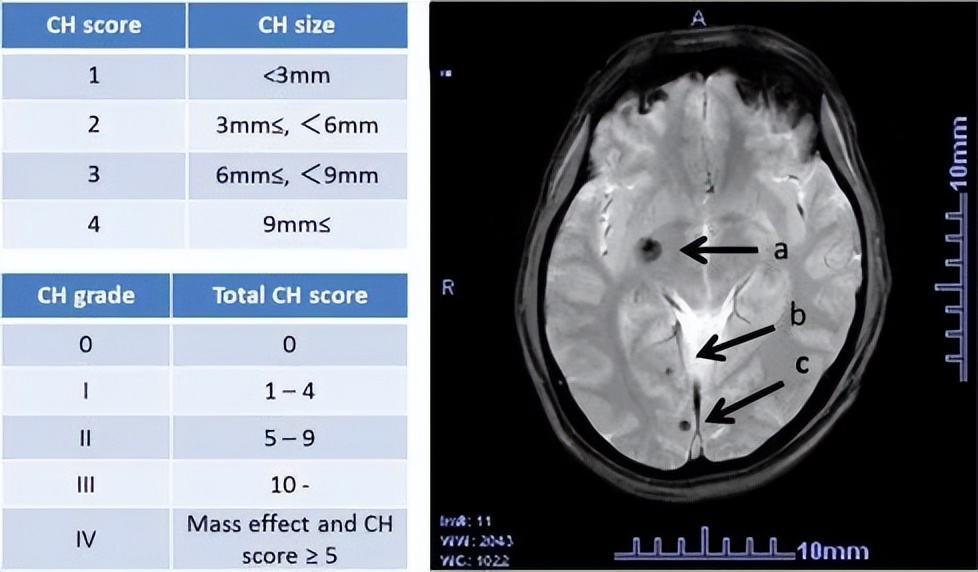

二、脑海绵状血管瘤出血风险如何评估?

脑海绵状血管瘤出血的风险评估对保守治疗和干预治疗的选择至关重要。尽管脑海绵状血管瘤出血在所有病例中的真实发生率仍然未知,但这种少见疾病在有症状的病例中出血率可能高达40%。 一些预测因素可用于评估脑海绵状血管瘤出血的风险。

首先,脑海绵状血管瘤的 首发症状为出血 和 病变位于脑干 时,出血风险较大。 脑干海绵状血管 瘤每年的出血率为10.6%,其中32%的脑干病变表现为脑出血。与其他部位的病变相比,脑干脑海绵状血管瘤的患者在诊断后的5年内出血的风险更高,为27.7%,而其他部位的病变仅有8.2%的出血风险。

因此,在对脑海绵状血管瘤进行治疗选择时, 评估出血风险是至关重要的 ,需 同时 考虑病变的首发症状、病变位置以及患者的出血史等相关因素。